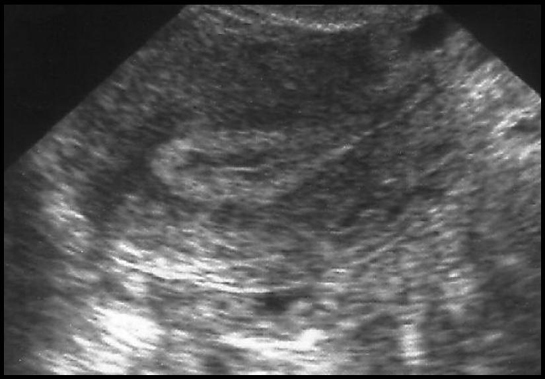

2ème partie de cycle ; épaississement échogène de la périphérie vers le centre ; hyperéchogène en fin de phase lutéale